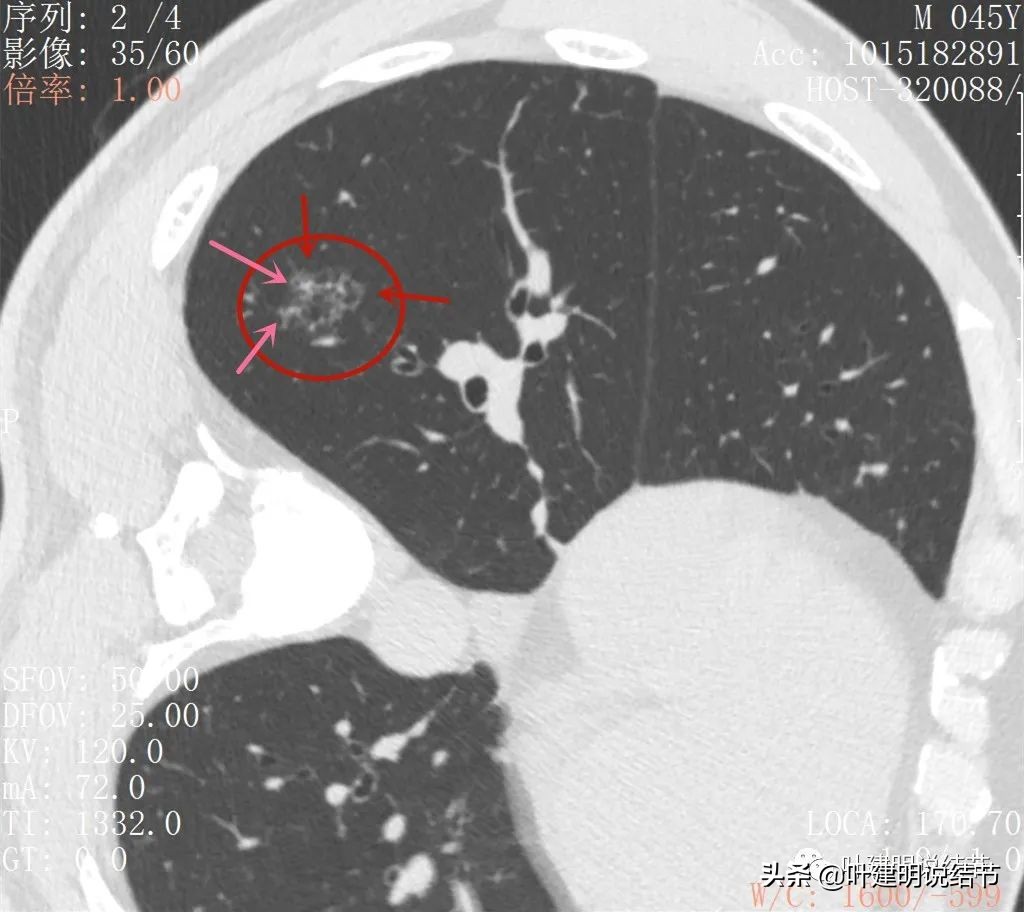

再来看薄层扫描:

边缘血管异常增粗(桔色箭头),边缘显糊(绿色箭头),细支气管扩张(黄色箭头)